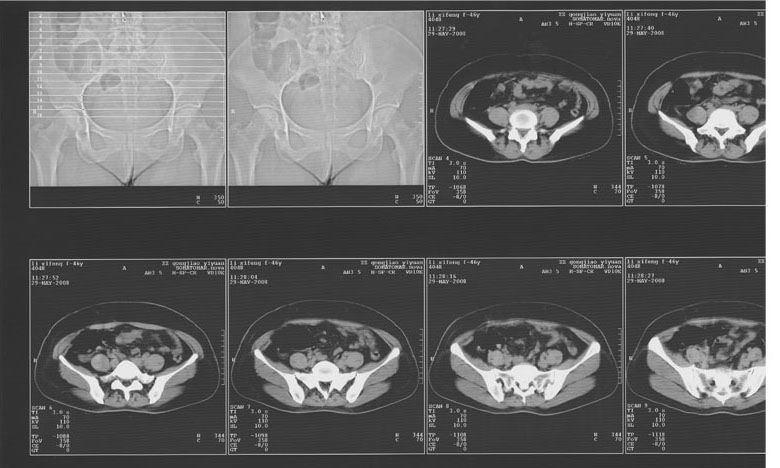

5年前子宫肌瘤 子宫切除,2年前整个下腹痛2周余病因不名,2008年5月底再次左下腹痛行ct,6月2日ct增强,请指教

不知道子宫切除术式是怎么样的?我看宫颈是健全的,子宫体下部部分残留,应该属于次全切吧?

我考虑是位于残留子宫体部的左侧又重新复发了一个肌瘤,中间似有坏死,b超或者彩超进一步检查吧!

肠管的断端还是宫颈后的残留?建议还是ct增强或彩超进一步检查.

是肠管影还是残留子宫子宫肌瘤复发可充分肠道准备后复查鉴别,也可结合b超检查。